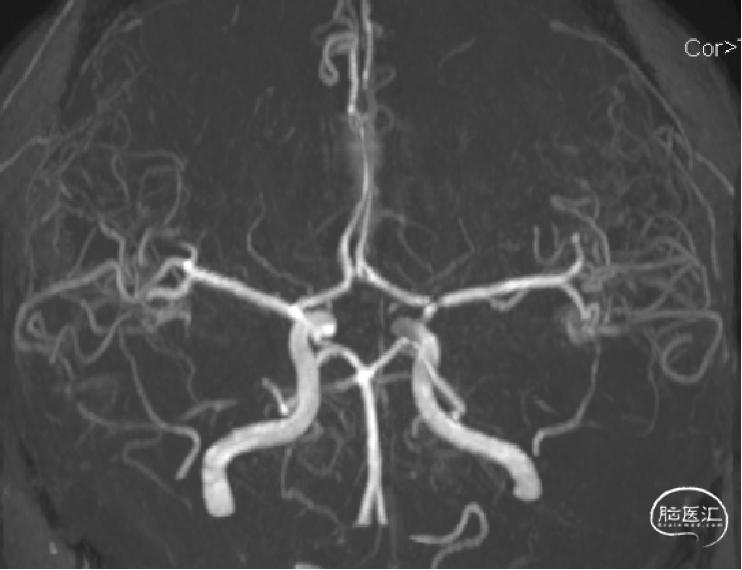

术后第三天头颅MRA示:血管通畅。

左侧颈总动脉正侧位造影

右侧颈内动脉正侧位造影

左侧颈内动脉后交通段动脉瘤整体大小约4.9mm×9.3mm,

子瘤约4.3mm×2.4mm,

主瘤体5.8mm×4.1mm,

瘤颈宽3.0mm,不规则